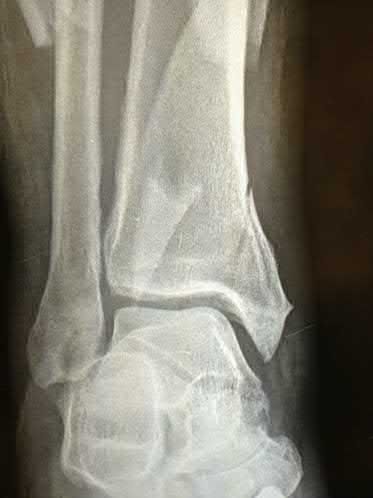

A 25-year-old female is involved in a motor vehicle collision. She presents with the isolated injury seen in Figures A through D. Her leg is swollen but her skin is intact. She has no clinical signs of compartment syndrome. Which of the following treatment options will allow for maintenance of fracture alignment and minimize the risk of soft tissue complications?

The patient presents with a closed distal third metaphyseal-diaphyseal distal tibia fracture with simple intra-articular extension. Immediate intramedullary nailing along with percutaneous fixation of the articular component provides appropriate restoration of length, rotation and alignment and minimizes the risk of wound complication.

Displaced distal third tibia fractures may be associated with simple intraarticular extension. Operative treatment of intra-articular distal tibia fractures has historically been performed with open reduction and internal fixation. Early open reduction and plate fixation of pilon fractures has been associated with high rates of infection and wound complication. In select patterns with simple articular extension, percutaneous screw fixation and medullary nailing may provide appropriate reduction with minimal soft-tissue risk.

Figures A and B demonstrate a distal third tibial shaft fracture with simple intra-articular extension. The axial and coronal CT cuts in Figures C and D further clarify the articular injury. Illustrations A and B demonstrate a comminuted distal third tibial fracture with simple intra-articular extension. Illustrations C and D are fluoroscopic images of the same injury after intramedullary nailing and percutaneous fixation of the articular component.